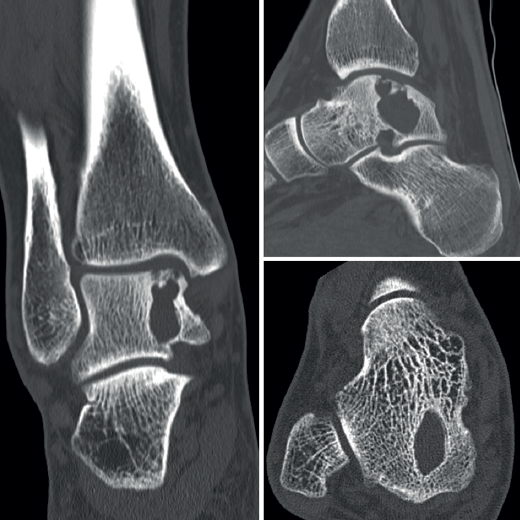

Se amplió el estudio con imágenes de la tomografía axial computarizada (TAC) que mostraron su extensión subcondral (Figura 3).

En las pruebas de imagen, la RM es la que mejor caracteriza estas lesiones. Muestra una señal hiperintensa en T2W, pueden delinearse niveles llenos de líquido y observarse múltiples septaciones internas. Permite valorar su extensión perilesional y el edema circundante. La TAC es útil para determinar la presencia de una fractura patológica.